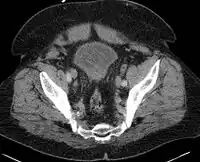

Acute bacterial prostatitis-Axial contrast-enhanced CT images demonstrate multiple prostate abscesses characterized by hypoattenuating regions with peripheral rim enhancement. The abscesses are confined within the prostate capsule and the entire prostate gland is enlarged.